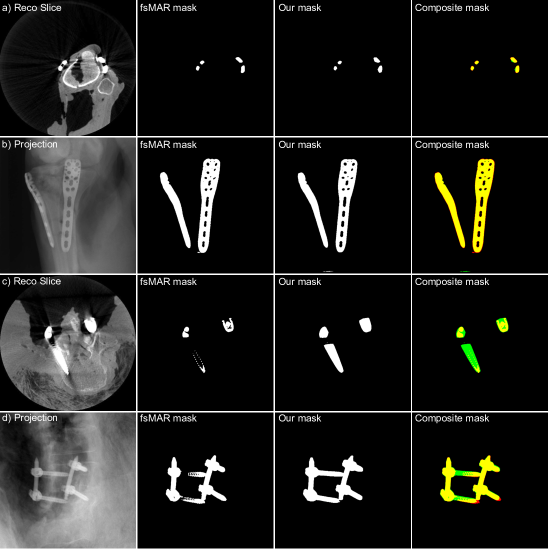

where MfsMARsubscript𝑀fsMARM_{\text{fsMAR}} denotes the binary 3D mask generated by the standard fsMAR and Mmod.fsMARsubscript𝑀mod.fsMARM_{\text{mod.fsMAR}} the binarized intermediate 3D mask of the modified fsMAR (cf. Fig. 3). To make sure that all metal implants are safely included in that joint mask, the proposed segmentation approach is parametrized (solely for creating that joint mask; that parameter set is not applied during inference of the test datasets) that it creates slightly overestimated masks. Therefore the network’s output threshold is set to 55-5 and the CF’s threshold for the amount of necessary consistency is decreased to 95%percent9595\%. Thus, an overall slightly grown joint mask is achieved. Two examples of the different MAR’s masks, as well as their joint mask, can be seen in Fig. 5. Examples of excluded regions masked by the joint mask can e.g. be seen in Fig. 8 where they are denoted with red outlines.

Refer to caption

Figure 5: The 1st column shows two examples, each shown as a 3D reconstruction slice (cf. a) and c)) and corresponding 2D projection (cf. b) and d)), where a) and b) correspond to the first example (knee) and c) and d) to the second example (spine). Whereas the 2nd column shows the threshold-based 3D masks and its corresponding forward-projected 2D mask extracted by the standard fsMAR, the 3rd column represents the respective proposed modified fsMAR masks. Moreover, the 4th row shows the composite/joint segmentation mask of both methods, which is used to mask the quantitative evaluation metrics as explained in Sec. 2.3.2. It can be seen, that the masks are widely comparable for the first example, whereas the masks for the second example vary drastically. This is due to the CBCT typical artifacts and the inability to segment the resulting vanishing metal structures in a 3D segmentation approach.